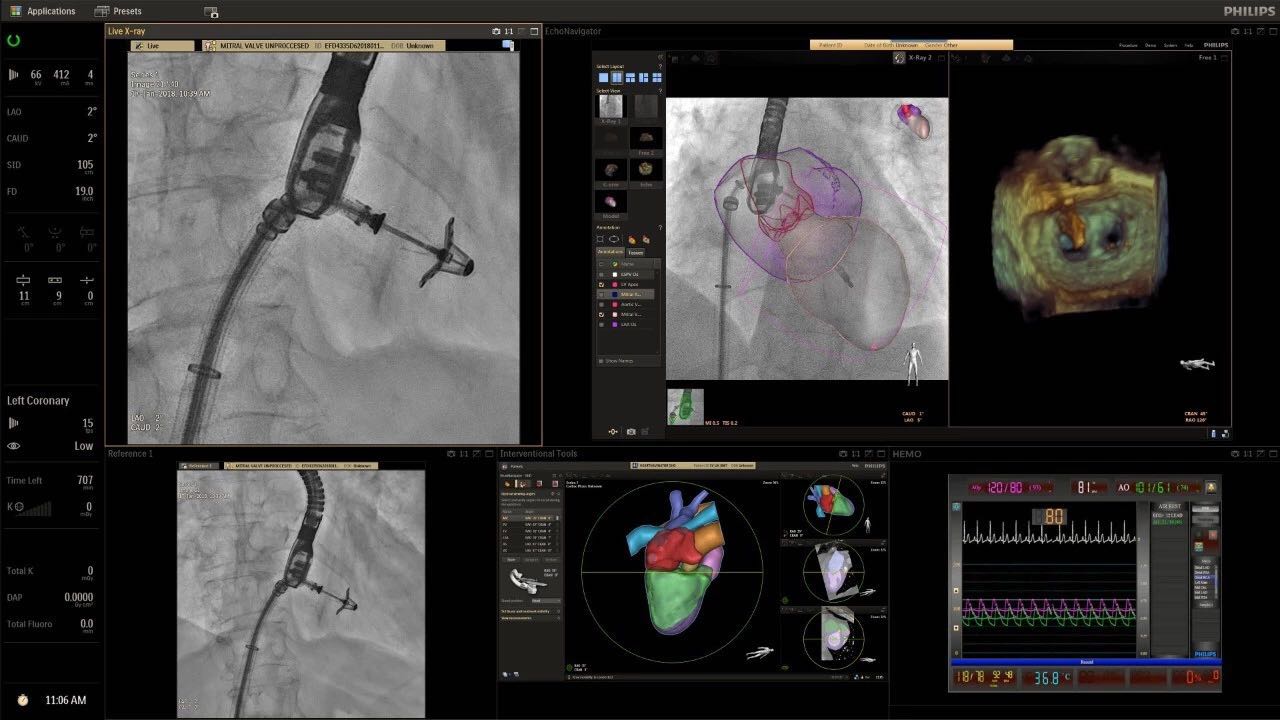

在日益復雜的干預期間,臨床醫(yī)生需要快速、輕松地可視化關鍵解剖結構并確定手術過程中患者的變化。2019年1月17日,飛利浦宣布推出采用FlexArm的Azurion 7 C20,旨在提高圖像引導程序的定位靈活性。

帶有FlexArm的Azurion 7 C20 包含一系列創(chuàng)新技術,使臨床醫(yī)生可以更輕松地在整個患者身上進行二維和三維成像。當臨床醫(yī)生移動系統(tǒng)時,圖像光束自動保持與患者的對準,允許更一致的可視化并使他們能夠將注意力集中在治療上。

(FlexArm C型臂可以沿著工作臺的兩側提供偏心成像。這允許醫(yī)生在左臂或右臂上進行徑向進入病例,完全或部分伸展,而無需移動患者或樞轉桌子。X射線束與手臂保持對齊,以促進其整個長度的平滑導航,而無需進行持續(xù)調整。)

飛利浦表示,采用FlexArm設計的Azurion 7 C20可提供卓越的靈活性和直觀的控制。該系統(tǒng)由智能運動引擎驅動,可在八個不同的軸上移動,所有這些軸均由其單個“Axsys”控制器控制。臨床醫(yī)生的模擬測試表明,該系統(tǒng)有可能顯著減少患者,工作人員和設備的重新定位,從而改善微創(chuàng)手術的可及性,包括通過患者手腕進入身體的手術(橈動脈入路),并降低患者的風險。無意中拔出電線和管子,以及節(jié)省大量時間。該系統(tǒng)非常適合混合手術室(OR),可滿足一個房間內的多種專業(yè)需求,例如手術和血管內手術的組合。

FlexArm在不少于8軸的情況下旋轉,從而創(chuàng)建幾乎無限的靈活性來執(zhí)行成像,從頭部到腳部在左側和右側進行2D和3D可視化。圖像光束保持與患者對齊,允許在旋轉或角度期間更好地可視化解剖結構。使用Axsys運動控制系統(tǒng)輕松操作支架。